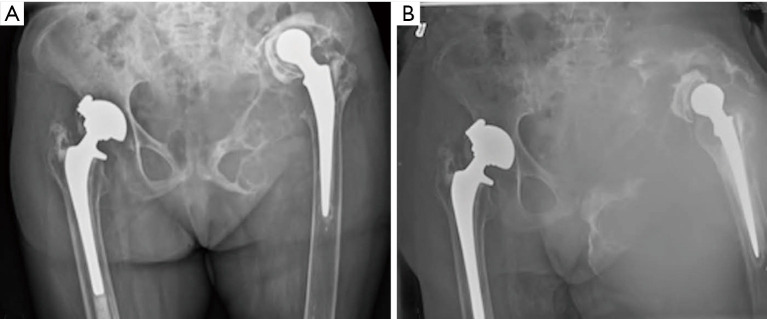

Background: The formation of destructive pseudotumors is a well-documented, albeit rare, complication of total hip arthroplasties. They tend to be progressive and, if left untreated, can result in extensive periprosthetic bony destruction. The current case presents a large benign mass consistent with a pseudotumor on both imaging and intraoperative findings but histologic findings demonstrating chronic hematoma.

Case description: An 86-year-old female with a metal-on-polyethylene total hip presented with a massive pseudotumor accompanied by extensive bony lysis. Due to pain and chronic anemia, a palliative debulking procedure was undertaken as a palliative measure. At one year follow-up, the patient reported significant pain relief and was able to ambulate safely with gait aids. Her hemoglobin stabilized post-operatively and ongoing transfusions were not required. Final pathology was not supportive of particle disease despite this being the leading diagnosis. Microscopic sections showed tissue mostly composed of fibrin and blood with multiple foci of calcification and reactive papillary endothelial hyperplasia which can be seen in chronic hematomas.

Conclusions: This case presents the diagnostic dilemma of a large benign mass consistent with a pseudotumor on both imaging and intraoperative findings but histologic findings consistent with a chronic hematoma. It highlights the importance of close follow-up and early intervention when periprosthetic osteolysis is detected.